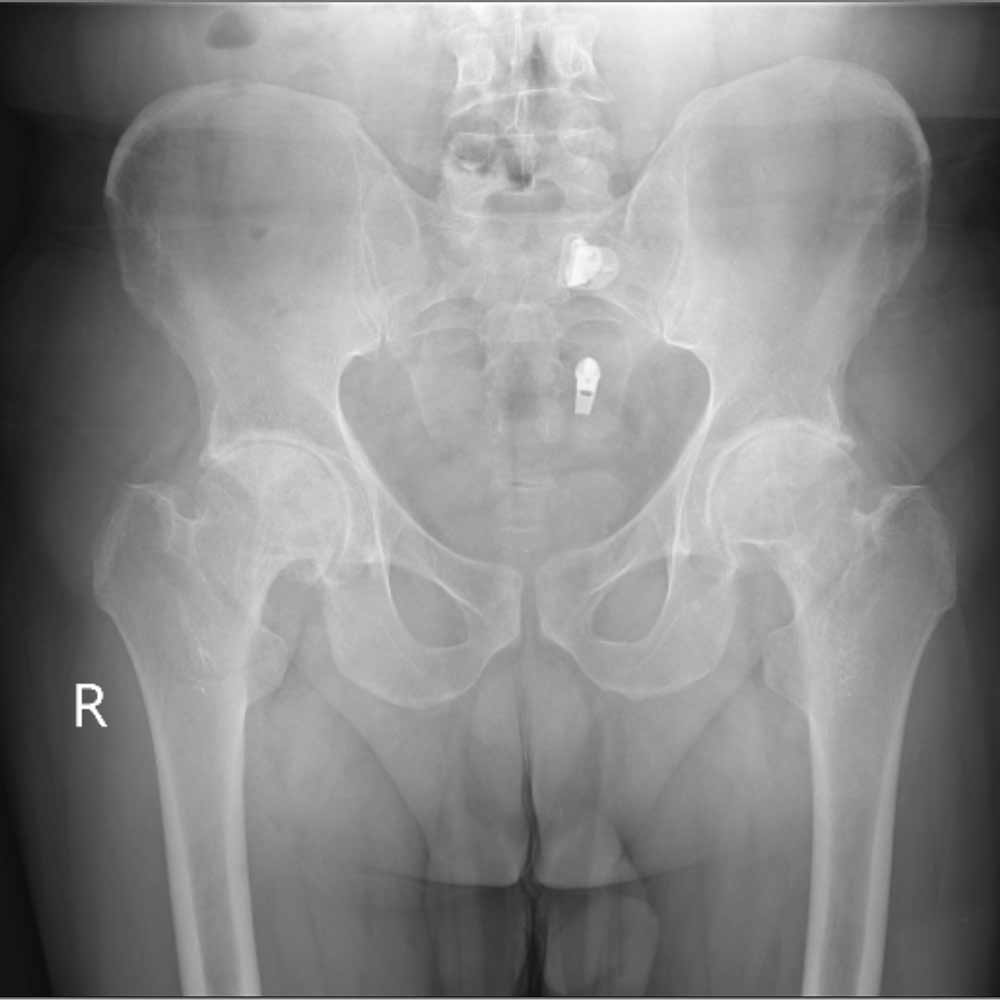

در نهایت، روش های تصویر برداری مثل رادیوگرافی به تشخیص بیماری کمک میکند. مهمترین روش تصویربرداری برای تشخیص ساییدگی لگن رادیوگرافی ساده است. تشخیص این بیماری نیاز به سی تی اسکن یا ام ار آی ندارد.

در تصویر رادیوگرافی از مفصل، چون غضروف نازک شده است فاصله مفصلی یا فاصله بین دو استخوانی که مفصل را تشکیل داده اند و در حد چند میلیمتر است کاهش پیدا میکند و در کناره های استخوان های تشکیل دهنده مفصل استخوان اضافی دیده میشود.

همچنین ممکن است کیست های استخوانی در بالای استابولوم یا در سر استخوان ران دیده شود.

در زیر تصاویری از عکس ساییدگی لگن در چند بیمار را میبینید. با کلیک بر روی هر کدام تصویر بزرگتری از آن را خواهید دید.